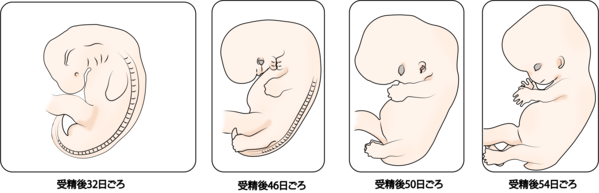

妊娠2か月の胎児 胎芽 の成長過程のイラスト素材176534691 毎月1点無料 フリー のストックフォト イメージマート。

妊娠6週目の症状気をつけること、赤ちゃんの大きさなど - 株式会社エバーセンス。

妊娠10週たまひよ 医師監修 妊婦の症状や体の変化、赤ちゃんの成長。